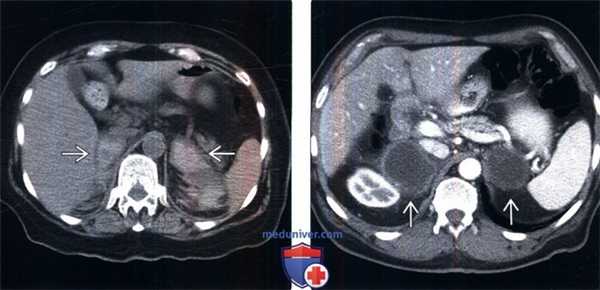

в) Дифференциальная диагностика надпочечниковой недостаточности:

1. Метастазы в надпочечниках и лимфома:

• Очаговые образования, как правило, без диффузного увеличения

2. Кровоизлияние в надпочечники:

• Гетерогенные контрастируемые образования (40-80 HU)

3. Туберкулез и грибковая инфекция надпочечников:

• Одностороннее или двустороннее увеличение надпочечников (острая стадия)

4. Аденома надпочечника:

• Может быть с обеих сторон

(Слева) У пожилой женщины на бесконтрастной КТ, выполненной для поиска причин артериальной гипотензии, гипонатриемии, гипогликемии и сепсиса, развившихся после артропластики коленного сустава, выявлено двустороннее кровоизлияние в надпочечники, что служит редкой причиной острой надпочечниковой недостаточности.

(Справа) У пожилого мужчины с раком легкого на КТ с контрастным усилением выявлены крупные некротизированные метастазы в надпочечниках. Данные лабораторных исследований (снижение уровня Na, повышение уровня К) и тест с АКТГ -стимуляцией подтвердили выраженную надпочечниковую недостаточность, которая была купирована поддерживающей терапией глюкокортикоидами.